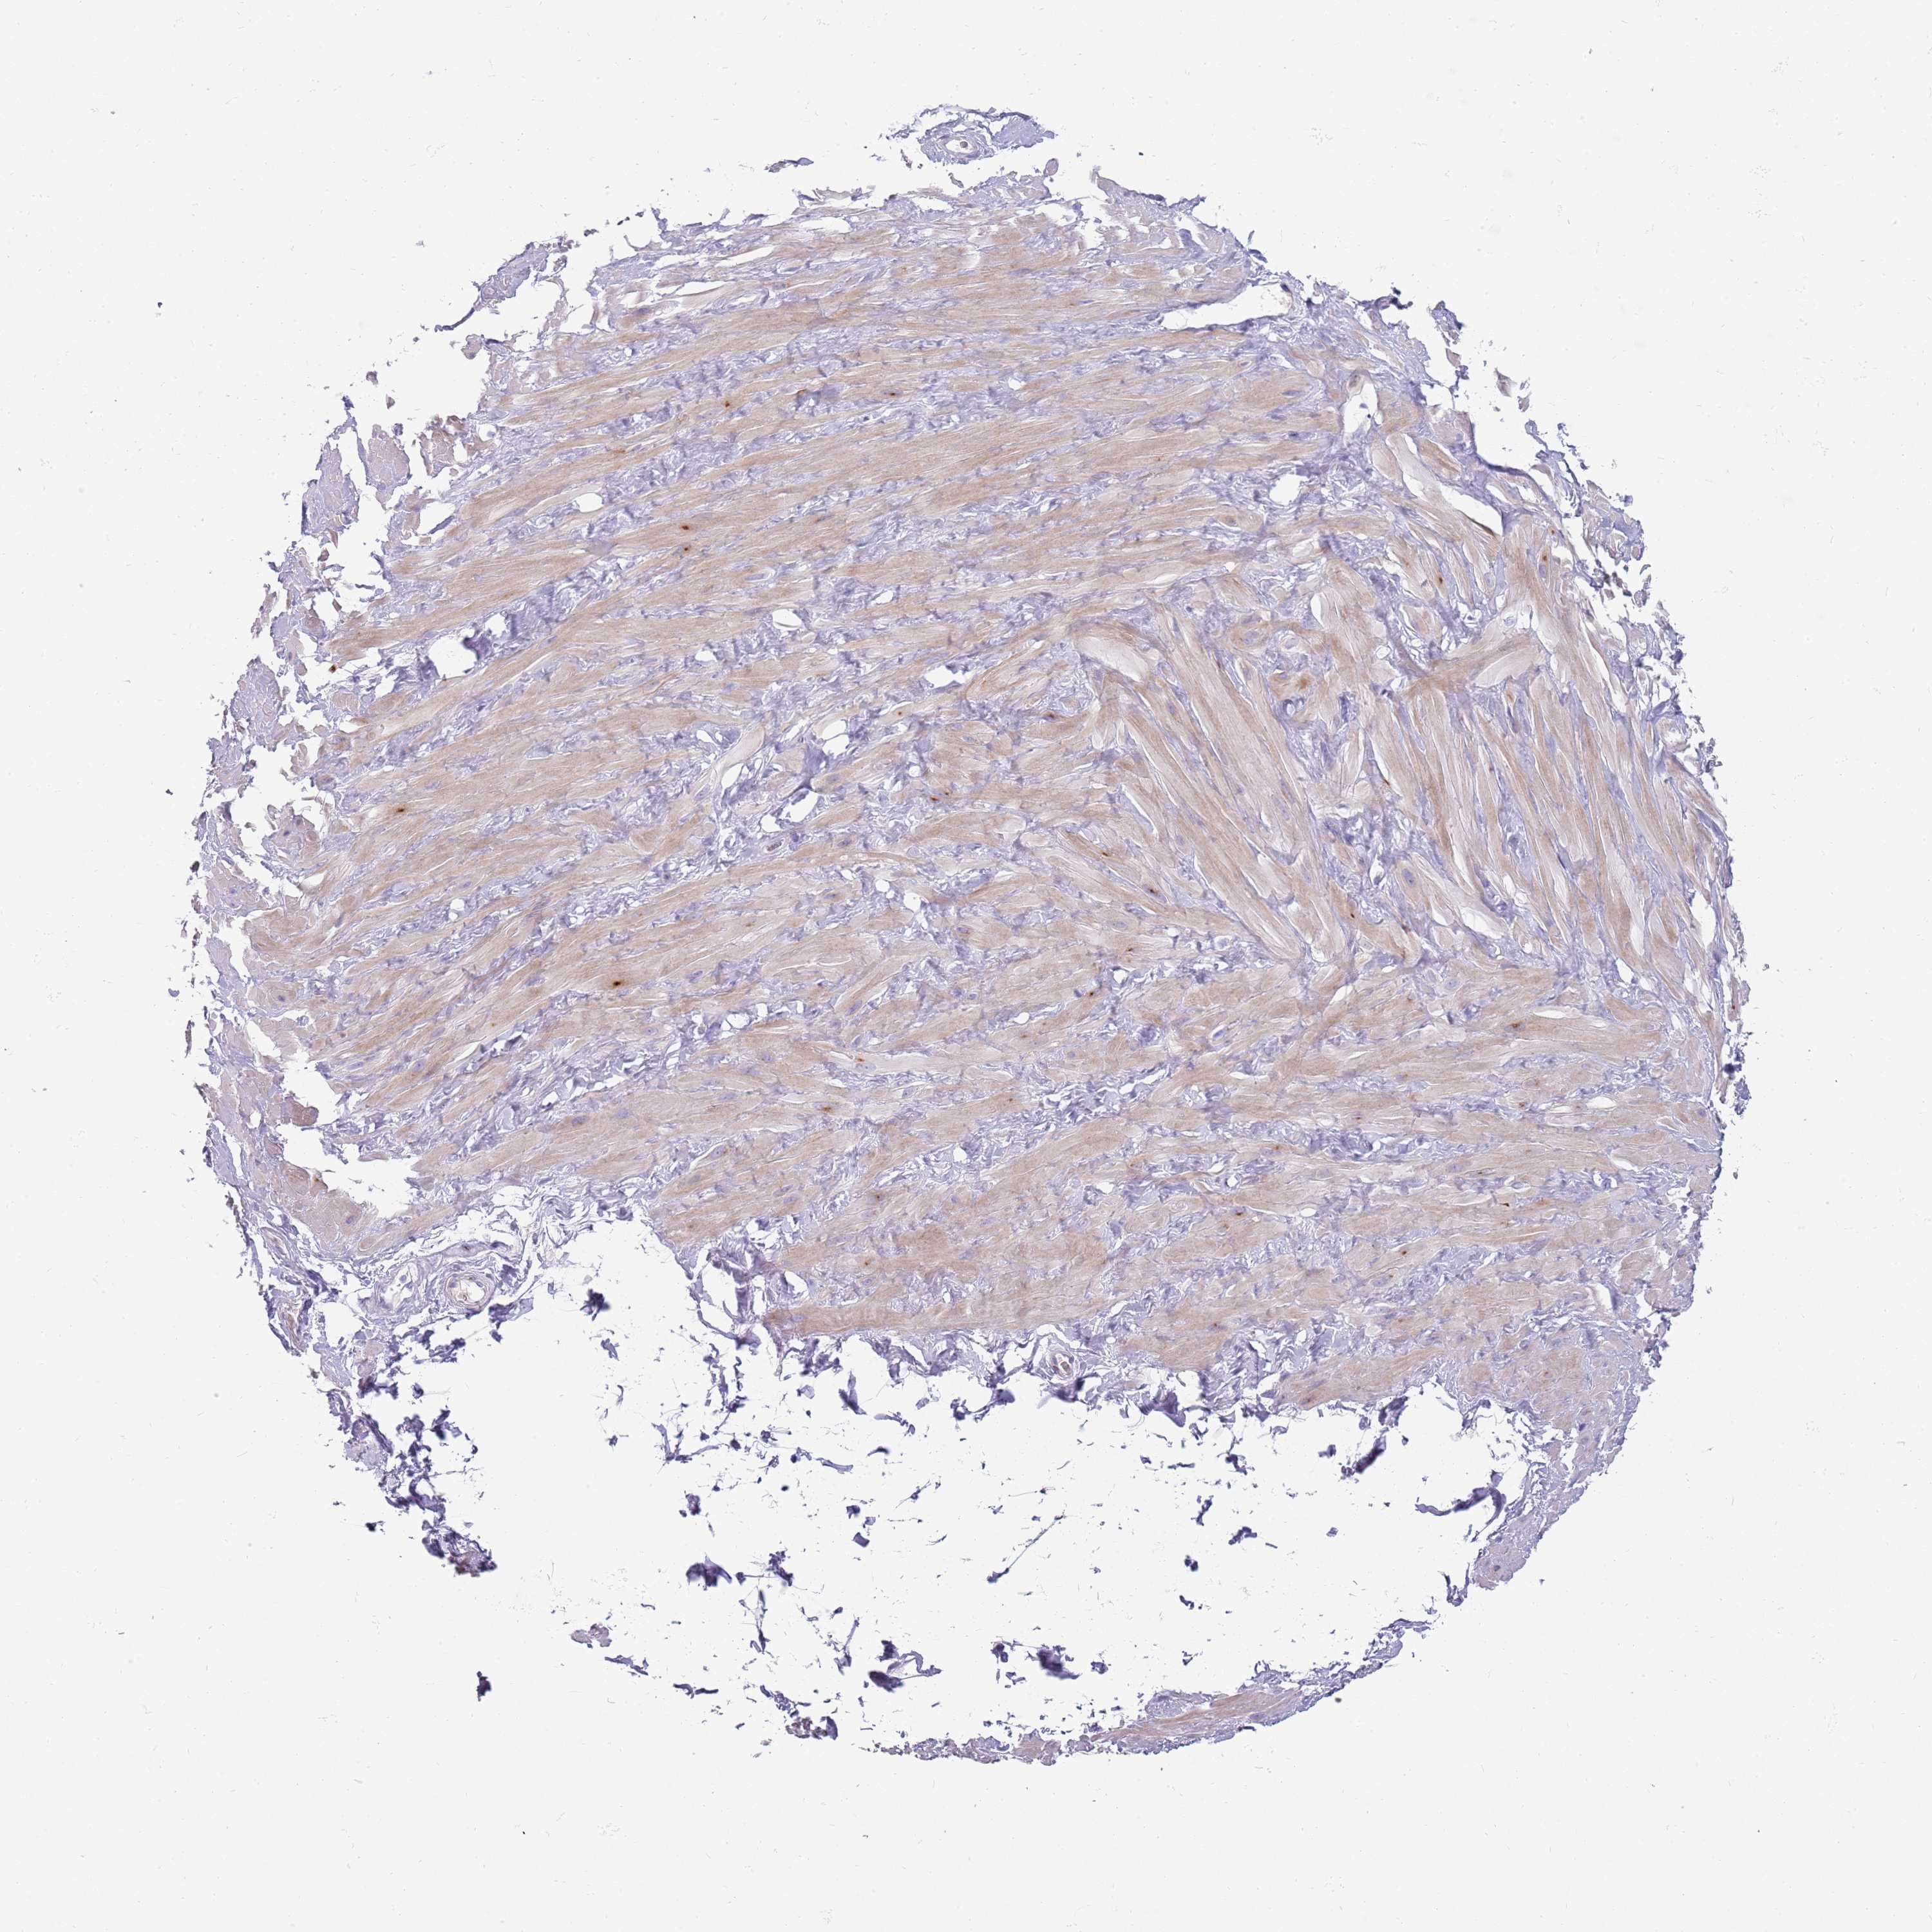

SULT2B1